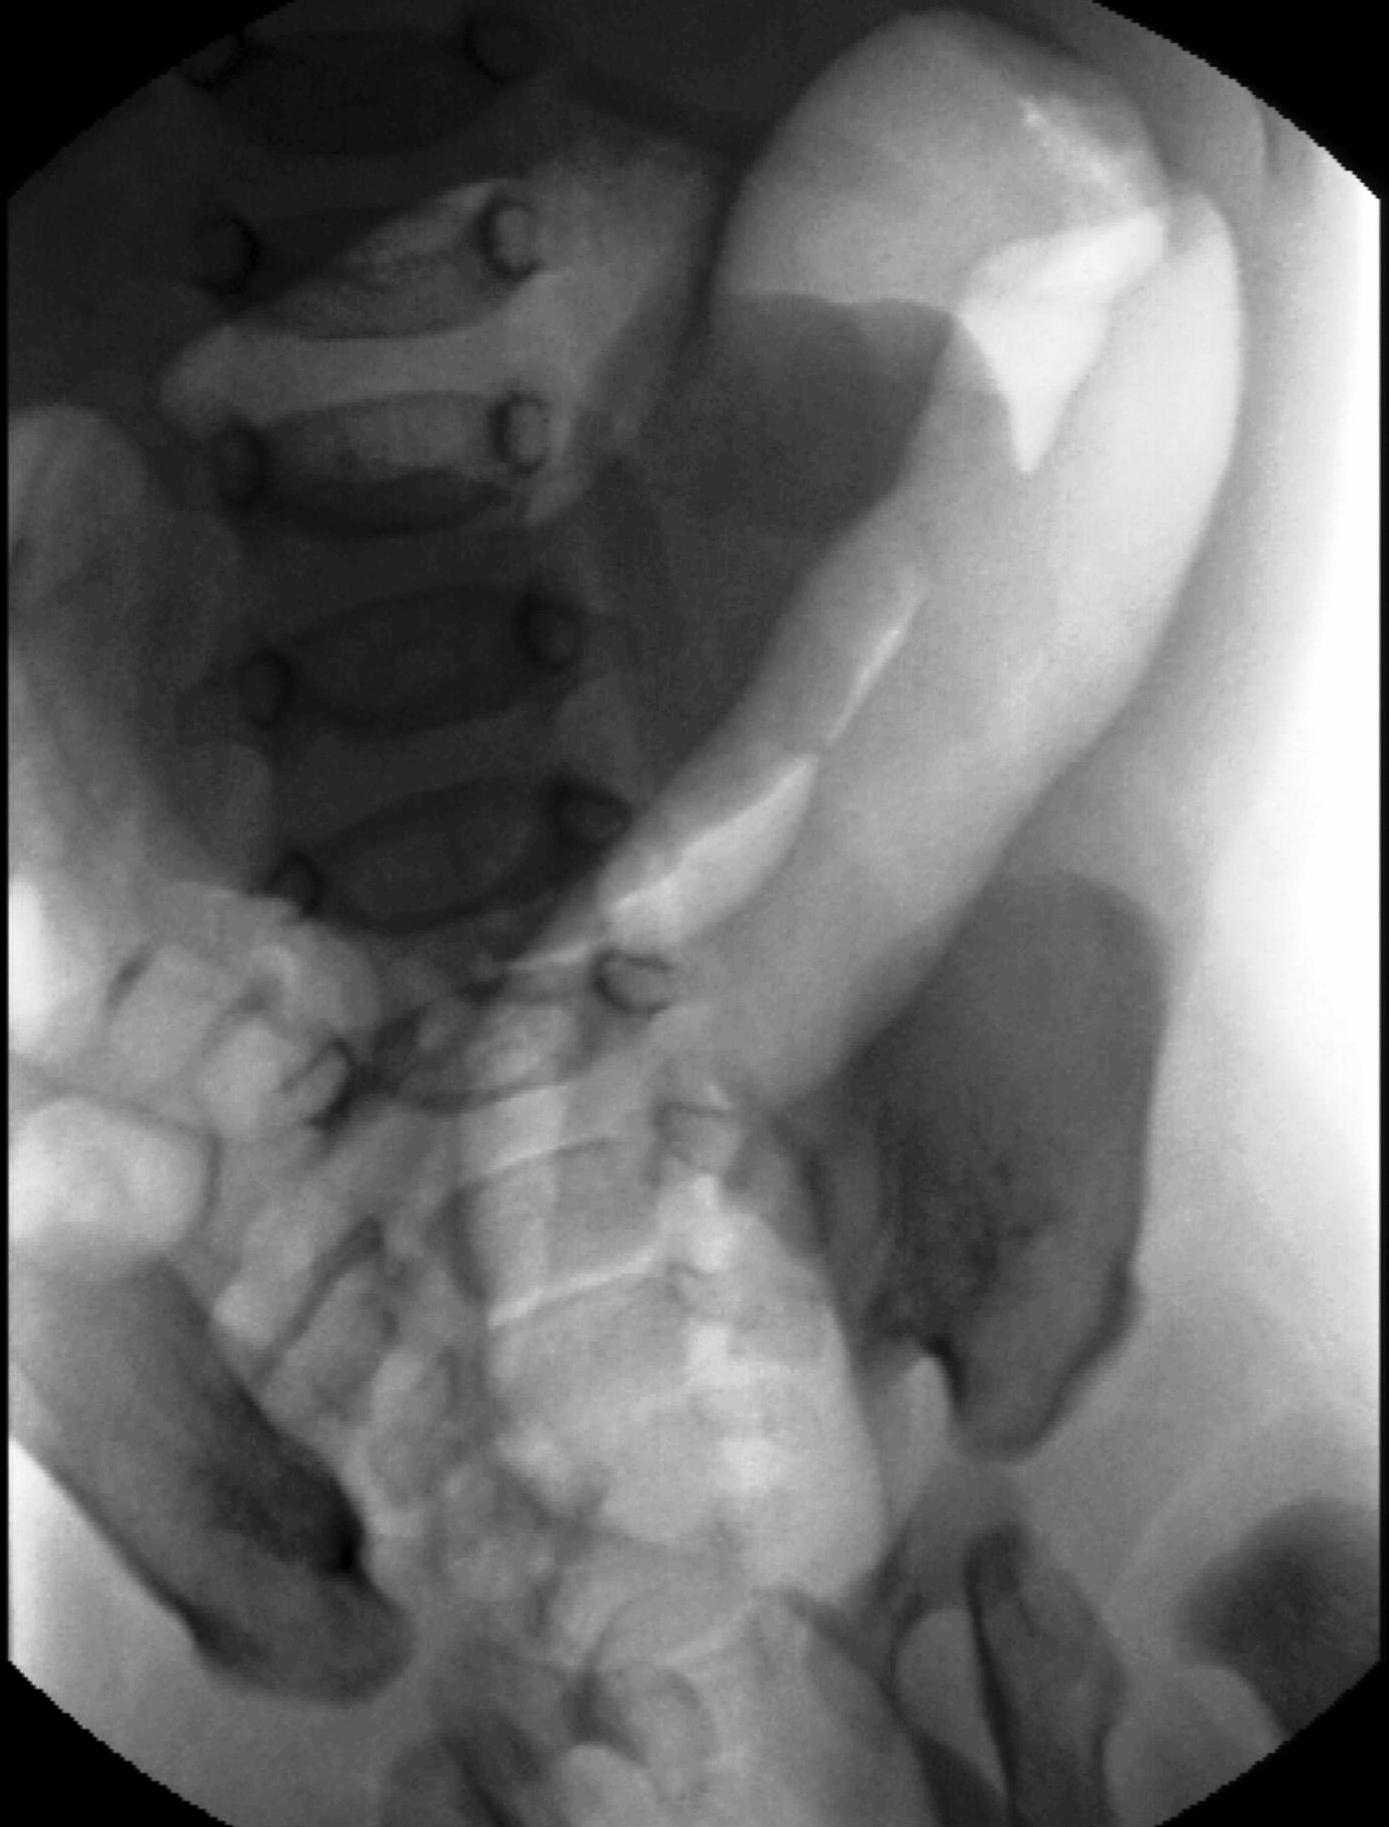

During X-ray examination the contrast material does not progress to the jejunal loops or it shows a “corkscrew” sign on the right side of the vertebrae as it piles up in the twisted intestinal loops.

Image

15. Contrast material empties the stomach slowly, small intestines are found on the right side of the abdomen. Malrotation-volvulus.